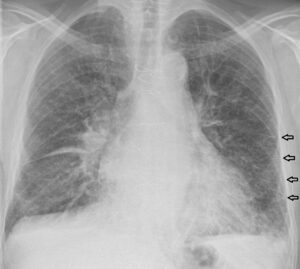

- Chest X-Ray (CXR

- Cardiomegaly

- Pulmonary Edema

Heart Failure Chest X-Ray

We’ll also do a chest x-ray, which could show a couple things. You may see the heart is actually enlarged because of the overload and stretch in the ventricles – and you may also see fluid in the lungs – that’s the pulmonary edema. We’ll also get an echocardiogram which can tell us things like end-diastolic volumes (remember that measures preload), ejection fraction, which is usually less than 50% in heart failure, and whether or not there are any valve issues.